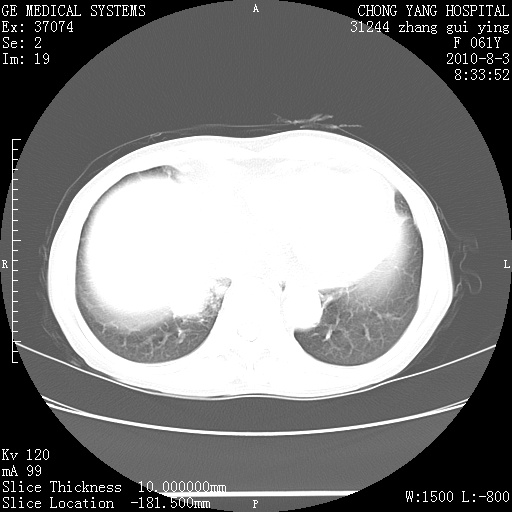

标题: CT28314:F61Y胸部增强,发热咳嗽一周入院,后面的为一周前平 [打印本页]

标题: CT28314:F61Y胸部增强,发热咳嗽一周入院,后面的为一周前平

双肺感染性病变,不除外合并结核感染。